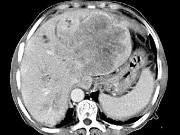

问题 女,73岁,中上腹痛1月余,患者黄疸、消瘦,CT检查如下图,最可能的诊断是()

选项 A.肝脓肿 B.巨块型肝癌 C.肝血管瘤 D.肝淋巴管瘤 E.肝胆管细胞癌

答案 B